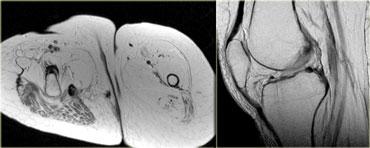

Hình bên trái là một ví dụ về bệnh cơ viêm.

Lưu ý tín hiệu tăng của tất cả các cơ ở tất cả các khoang.

Đây là hình ảnh phù nề.

Ngoài ra còn có phù nề ở tổ chức dưới da.

Rất hiếm khi chấn thương, chẳng hạn, lại biểu hiện phù nề ở tất cả các khoang.

Không có ổ tụ dịch bên trong cơ, nhưng cần lưu ý các ổ tụ dịch quanh mạc cơ.

Hình bên trái là một bệnh nhân viêm cơ.

Một lần nữa chúng ta thấy nhiều khoang bị tổn thương, phù nề lan rộng, tổn thương da và tụ dịch quanh mạc cơ.

Hình ảnh không đặc hiệu nhưng có thể gợi ý viêm cơ. Viêm cơ viêm thường có tính chất đối xứng hai bên.

Các đặc điểm MRI của viêm cơ bao gồm: cấu trúc bình thường trên chuỗi xung T1W, phù nề dạng lông vũ kèm ngấm thuốc, lưới hóa da và các bất thường KHÔNG giới hạn theo giải phẫu khoang hoặc thần kinh cụ thể.

Hình bên trái là một bệnh nhân viêm đa cơ (PM), một trong các thể bệnh cơ viêm.

Các cơ lớn ở gốc chi bị tổn thương, thường theo hình thái đối xứng.

Nhìn chung, không phải tất cả các cơ đều bị tổn thương, do đó MRI có thể giúp xác định vị trí tốt nhất để sinh thiết.

Đôi khi MRI toàn thân được sử dụng để chẩn đoán và theo dõi viêm đa cơ sau khi đã bắt đầu điều trị bằng corticosteroid.

Hình bên trái là một bệnh nhân viêm cơ thể vùi.

Lưu ý tổn thương đối xứng của cơ tứ đầu đùi và sự vắng mặt của phù nề ở các tổ chức xung quanh.